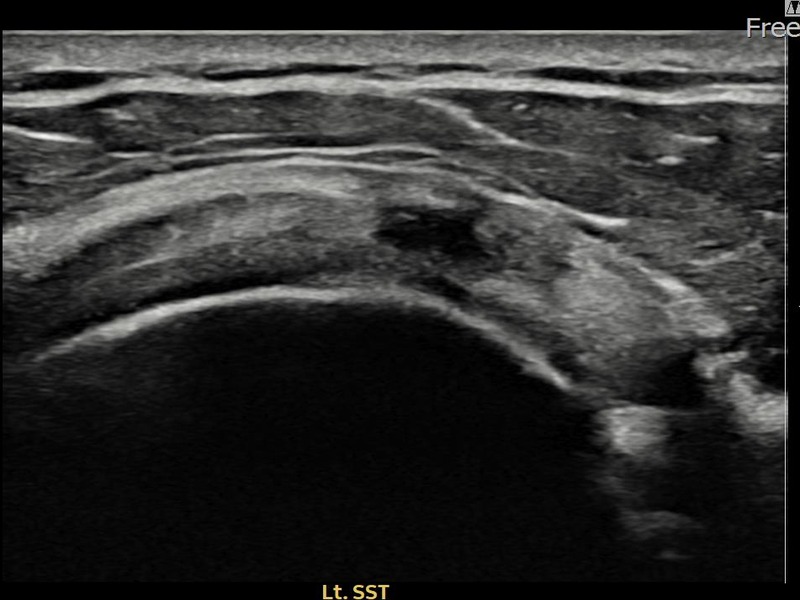

김ㅇㅇ님 · 좌측 극상근건 광범위 부분파열

좌측 어깨 광범위 파열로 수술을 권유받았으나 비수술 치료를 원해 내원하셨습니다. 초음파 검사에서 극상근건 전층에 걸친 광범위 부분파열이 확인되었으며, 어깨인대 축소봉합술 후 구조적 안정화와 기능 회복이 이루어졌습니다.